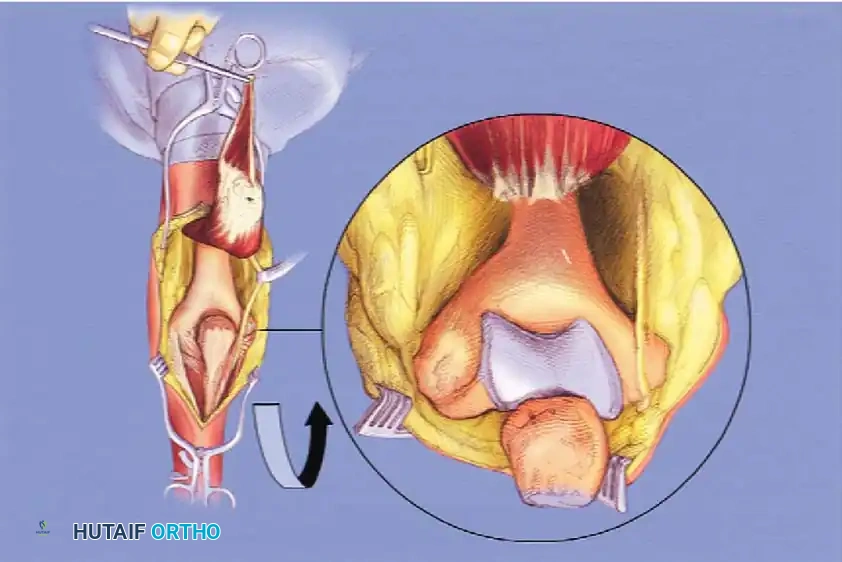

Image

Fig. 9: Triceps-reflecting anconeus pedicle (TRAP) approach. Access to the distal humerus is comparable to an olecranon osteotomy without violating the joint.